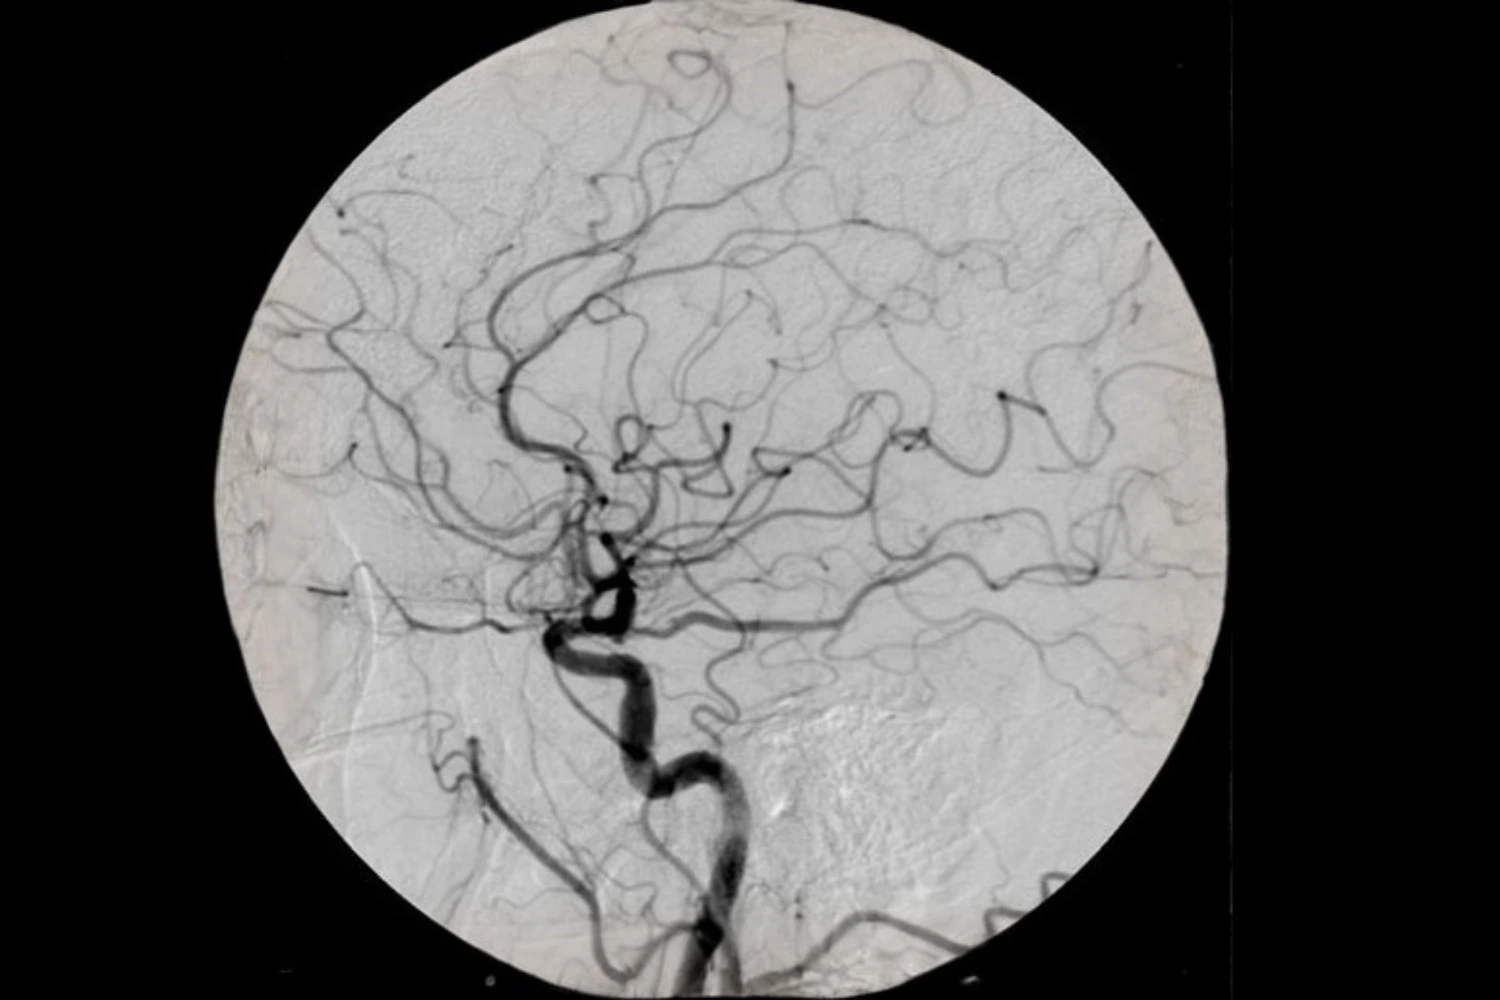

On the Vascular Interventions, the following procedures are carried out routinely like – Digital Subraction Angiographies, Splenogram, Venogram and Cavernographies.

Besides Interventional procedures, Cerebral Angioplasties and Embolizations, Biliary Drainages/Stentings, Urostentings are also done routinely.